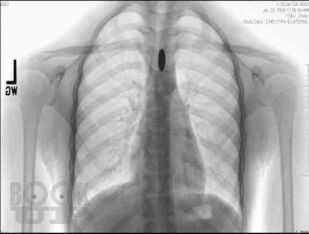

Сборник включает вызвавшие наибольший интерес аудитории лекции и доклады на различных научно-практических конференциях в 2017–2018 гг. по актуальным проблемам пульмонологии и аллергологии детского возраста, таким как: современные методы диагностики и лечения, острые и хронические инфекционно-воспалительные и аллергические заболевания органов дыхания, муковисцидоз, туберкулез органов дыхания, а также обмен опытом, интересные случаи из медицинской практики, различные другие информационные материалы. Ежегодник адресован практикующим детским пульмонологам и аллергологам.